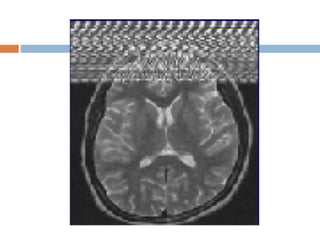

Aliasing artifact or wraparound It occurs when the dimensions of the body part being imaged exceed the FoV.  The part beyond the FoV is projected to the other side of the image.  It is caused by under sampling in the phase encoded direction.  Choosing an FoV that is smaller than the area imaged leads to wraparound or aliasing artifacts.

 Appearance  signalsfrom outside the FoV seen in the imaging volume.  Solution  Larger FoV and oversampling  Use saturation bands outside the FoV.